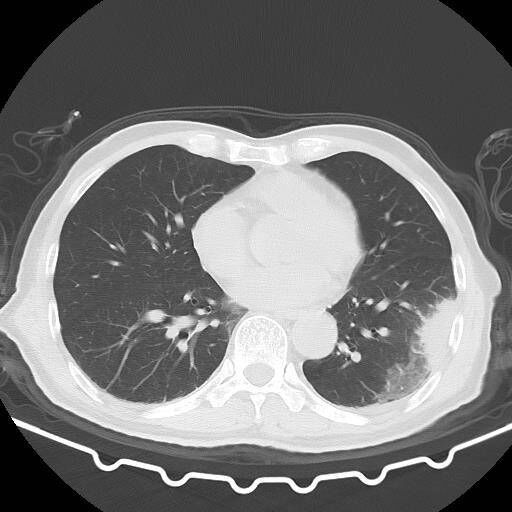

呼吸内科侯善群副主任医师接诊患者时,发现廖大叔神智不清,呼吸困难,口唇发绀,CT显示双肺大片肺炎,考虑衣原体肺炎。得知患者起病前有杀鸡经历,侯善群更加坚定了自己的判断,立刻给患者进行了支气管镜检查,肺泡灌洗液送检基因检测(NGS)。果不其然,导致其疾病的元凶正是一种名为"鹦鹉热衣原体"的微生物,也就是说,患者感染了鹦鹉热。